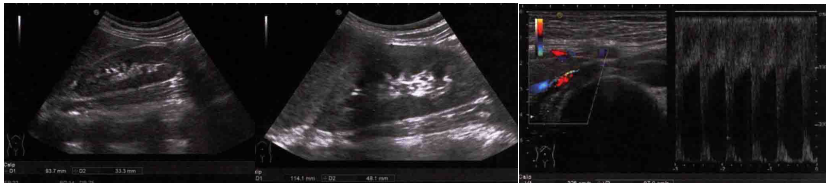

血管超声(图2):双侧颈动脉、椎动脉及上肢动脉系统未见明显异常。右肾体积偏小,右肾动脉中段局部管腔狭窄,收缩期峰值流速(PSV)达225 cm/s,与腹主动脉PSV比值为3.4:1。结合临床表现,首先考虑肾动脉FMD。左肾、左侧肾动脉未见明显异常,但左肾静脉局部明显扩张,符合“胡桃夹综合征”表现。

图2. 双肾及肾动脉超声